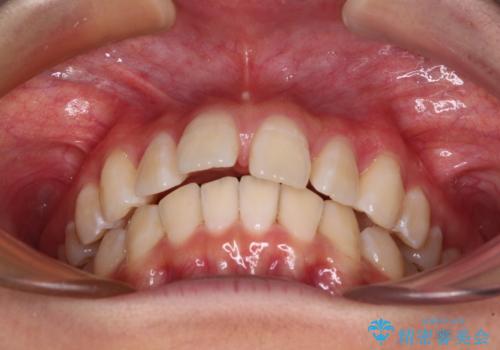

深い咬み合わせで前方に煽られた前歯 高校生のインビザライン矯正治療

奥歯の咬み合わせを見ると、上顎が下顎に対して相対的に前方にありました。

咬み合わせも深くなっていたため、上顎臼歯を後方に移動させつつ、下顎の小臼歯を直立させ、奥歯の咬み合わせを改善する必要があります。

インビザライン単体で対応することも検討できますが、達成する可能性が低いため、カリエールディスタライザーという補助装置を併用して、より確実性を上げることとしました。

奥歯の咬み合わせと深い咬み合わせを改善した後、隙間などをインビザラインで整えることとしました。